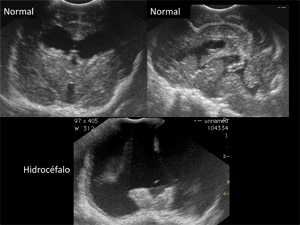

Imágenes de la especialidad